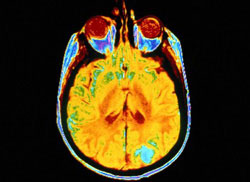

Des techniques d'imagerie cérébrale nouvelle génération

L'imagerie cérébrale est particulièrement difficile de nombreux points de vue et est également handicapée par des problèmes de faible résolution, qui provoquent une «contamination» de l'image par les structures environnantes. Le problème est encore plus manifeste lorsqu'il y a une atrophie, comme dans la maladie d'Alzheimer. Le projet PVEOUT financé par l'UE a entrepris de développer les technologies existantes et de surmonter les limitations actuelles afin d'obtenir des images fonctionnelles d'une plus grande précision. La forme et la taille des images fonctionnelles peuvent être corrigées sur la base des structures cérébrales correspondantes. La nécessité de valider ces images fonctionnelles et leur analyse a conduit à l'utilisation de «fantômes cérébraux» anthropomorphiques, qui consistent essentiellement en des mannequins ressemblant à l'homme. Ces fantômes physiques ont permis aux chercheurs et aux praticiens d'«acquérir un certain contrôle» sur la forme de l'objet et les propriétés des matériaux. Par conséquent, l'utilisation de fantômes évolués pourrait accroître le champ d'application des technologies disponibles et établir de nouvelles normes pour l'industrie du diagnostic. Des chercheurs de l'IBB-CNR, en Italie, ont mis au point un nouveau fantôme anthropomorphique à plusieurs compartiments appelé STEPBrain et adapté à l'imagerie PET/SPET et CT/MR. STEPBrain semble être unique au niveau mondial et a été créé pour contenir des compartiments distincts et indépendants, un pour la matière grise et l'autre pour la blanche. STEPBrain peut être utilisé pour valider diverses méthodologies de correction de l'effet de volume partiel dans des images de faible résolution et est peut-être la seule application à couvrir cet aspect. À ce titre, le potentiel de STEPBrain est donc énorme. Les développeurs sont désireux d'attirer des licences émanant de l'industrie du diagnostic et sont prêts à discuter d'une série de modèles de collaboration.